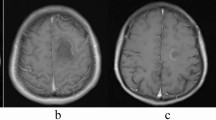

Clinical, neuroradiological and necropsy findings are described in a 52-year-old man with tumefactive fulminant demyelination of the spinal cord. Progression of the demyelination process produced paraplegia, mild paresis of the right upper limb, neurogenic bladder and sensitive loss over 2 weeks. MRI scans revealed several ovoid lesions in cervical segments and tumefactive T2-hyperintense signals with oedema and post-contrast enhancement located in thoracic segments Th3 to Th6. Cerebrospinal fluid (CSF) examination displayed lymphomonocytic pleocytosis with normal proteinorhachia, positive CSF oligoclonal IgG bands (OCB) and elevated IgG index (1.55). Serum anti-AQP4-Ab was not tested. Stored frozen CSF samples were later repeatedly examined with negative findings of anti-AQP4-Ab. Treatment with high-dose methylprednisolon and plasma exchange had limited effect. Immunosuppressive medication was interrupted because of an acute urinary infection. The patient died suddenly because of pulmonary embolism as a secondary complication. Histopathology of the spinal cord confirmed active demyelination. We considered that tumefactive demyelination could be a variant of neuromyelitis optica.